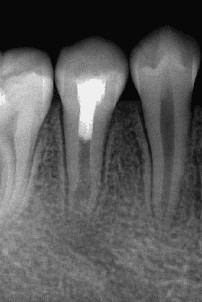

术后6个月